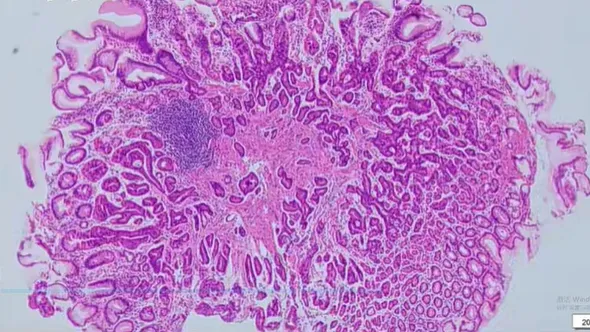

【“胃底腺型腺癌 / 泌酸腺腺瘤”的镜下特征】:结构异型+两种细胞特征

• 分化程度分化极好,形态接近正常胃底腺细胞;以主细胞为主型,壁细胞多分布于肿瘤边缘 / 表面。

• 异型性细胞异型性极低,仅见胞增大、密度增高,可复层 / 多层排列;核从基底层上移,核分裂像罕见。

• 增殖活性Ki-67 阳性率多小于 5%。

组织结构

• 腺体结构复杂,相互吻合形成 “endless glands”(无尽腺体);少见筛状结构,无坏死

与正常组织的关系与周围正常组织似乎有过渡(分界不绝对清晰

背景粘膜接近正常,无肠化、无萎缩

肿瘤间质表现为正常、水肿或粘液变,无促纤维间质反应

主要由主细胞分化细胞构成,细胞呈柱状,胞质偏嗜碱性,腺体具有明显结构异型,包括不规则分支、扭曲等,与周围正常胃底腺明显不同。低级别胃底腺型肿瘤包括OGA和GA-FG,二者具有相同的临床及病理特征,鉴别点为是否伴有黏膜下浸润。OGA为具有胃底腺分化的位于黏膜内的上皮性肿瘤。GA-FG为具有胃底腺分化的低异型性分化型腺癌,伴有黏膜下浸润。